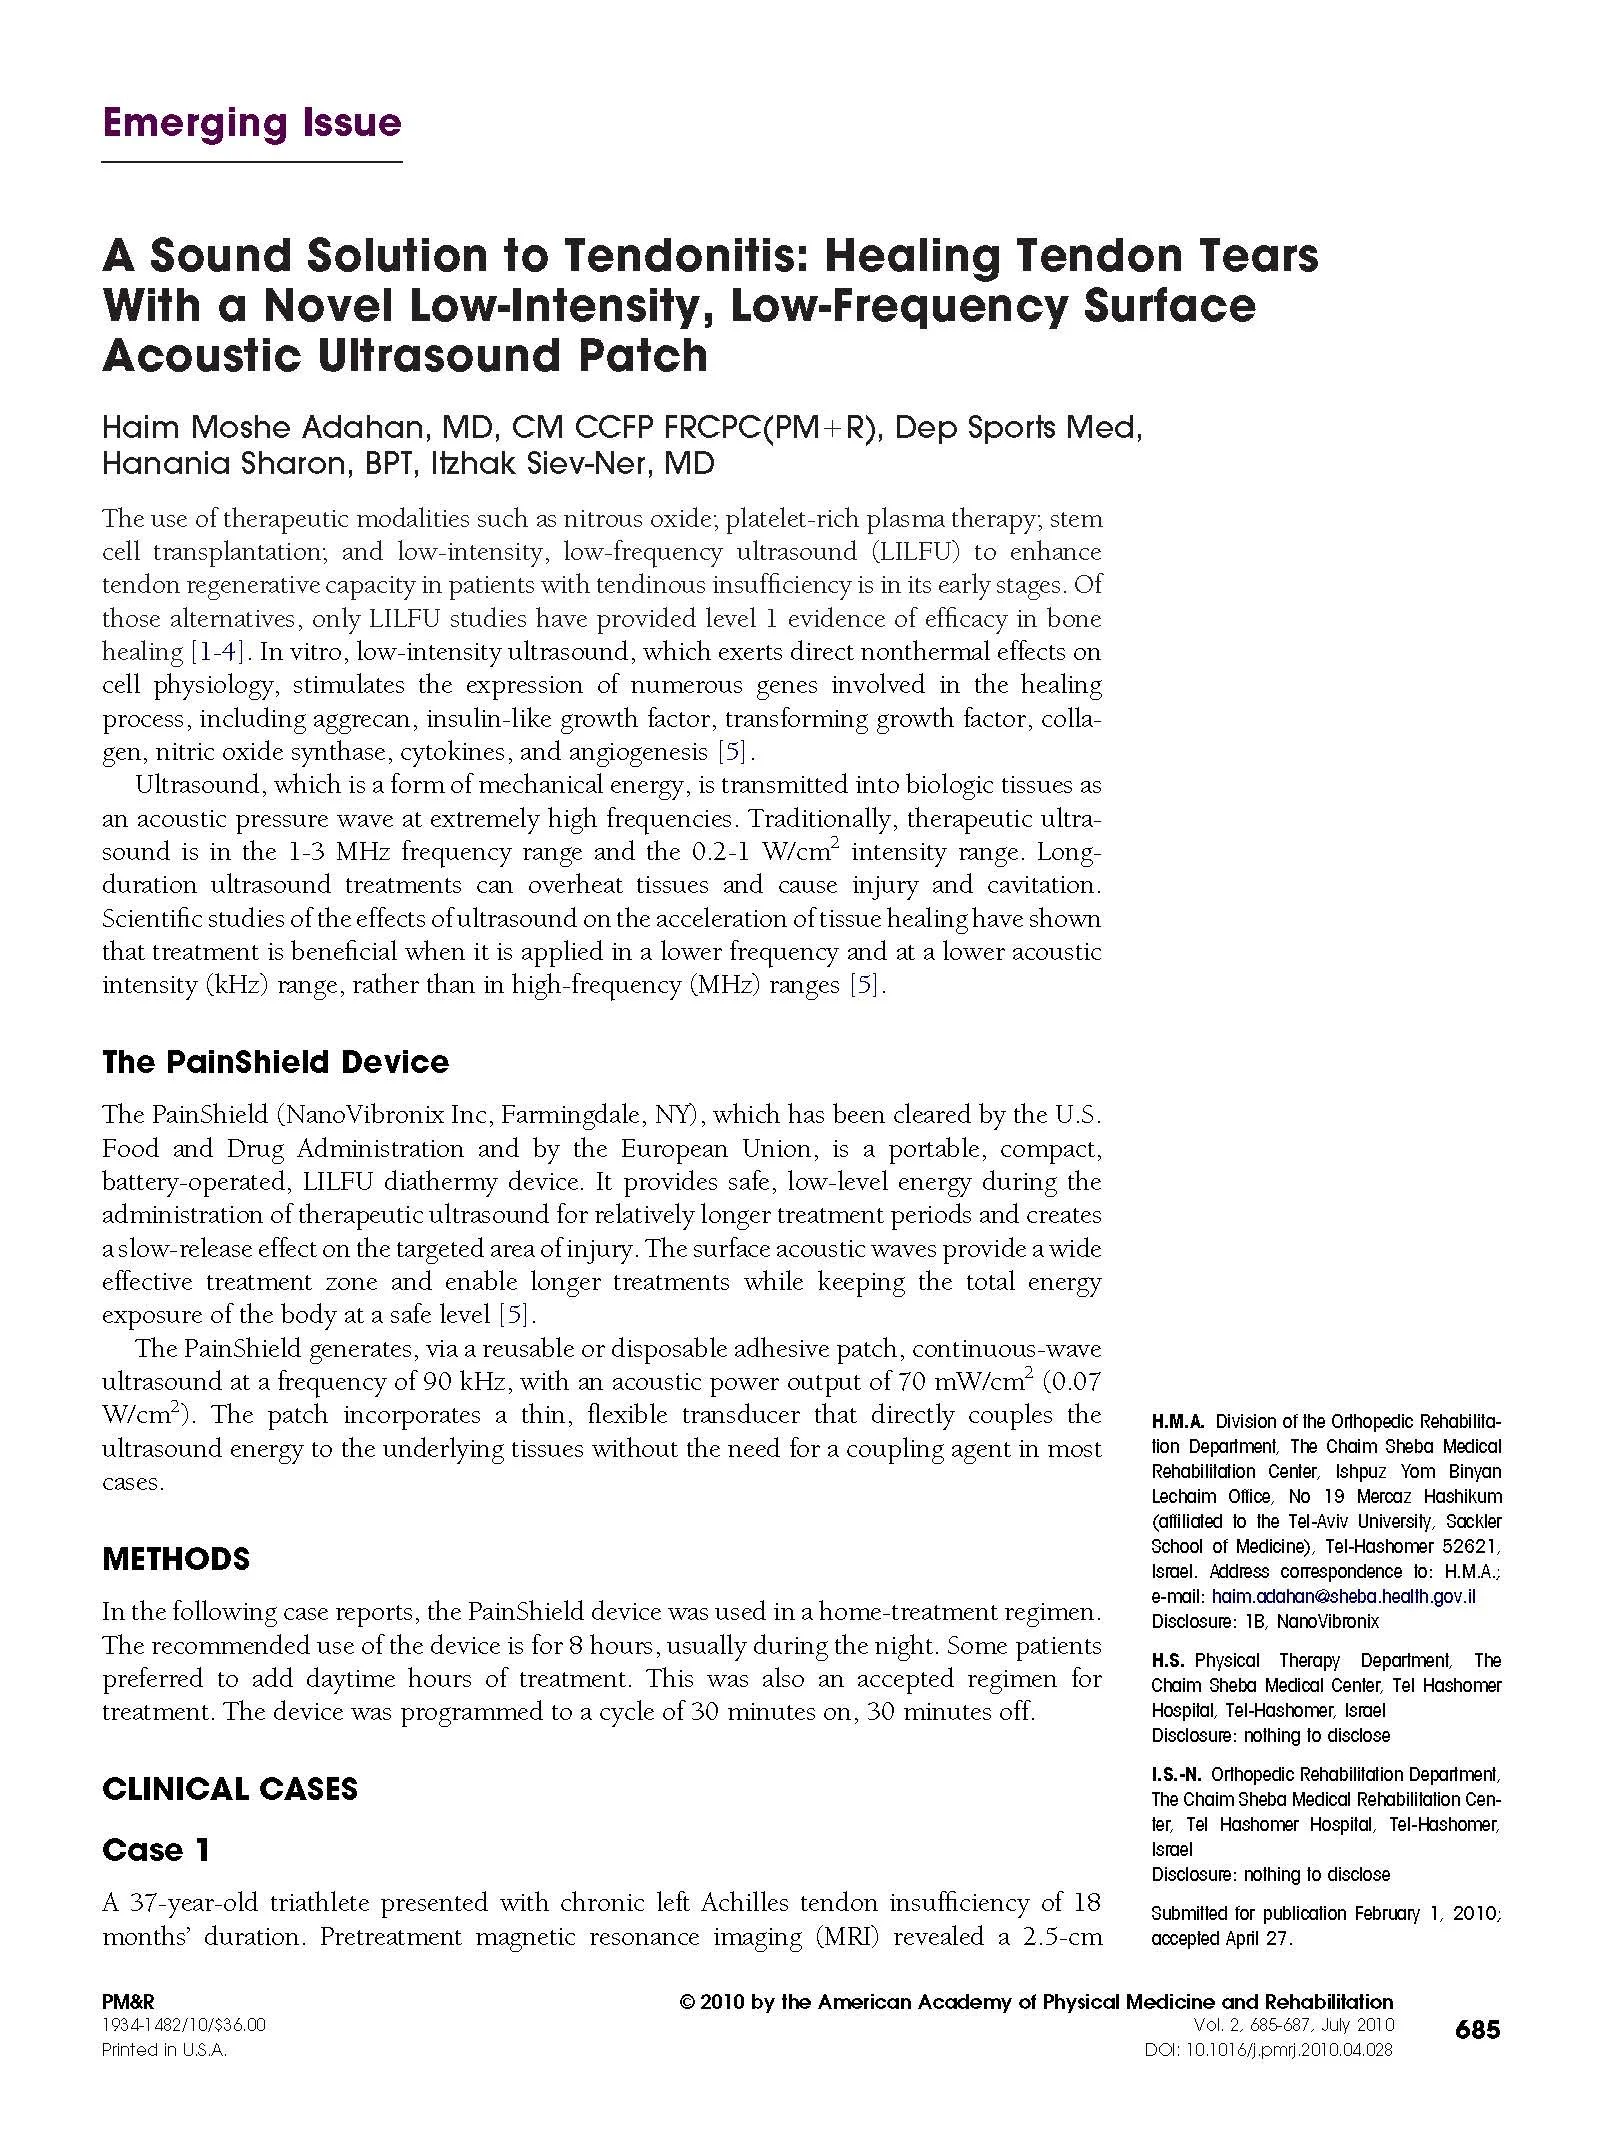

PainShield MD in the Treatment of Tendonitis

An Alternative Therapy to a Common Orthopedic Presentation

Clinical Evidence of the Improved Healing Outcomes of Ultrasound Therapy on Tendinopathies